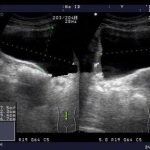

盆底也叫盆膈,分为前中后三部分,阴式分娩时有些人造成了盆膈损伤,当然损伤的部位不同,引起的体征也不一样。

前盆底是支撑尿道和膀胱的,如果损伤就会出现尿失禁或尿潴留,用Birtch或TOT手术治疗。

中盆底是支撑阴道和子宫的,如果损伤松弛,就引起阴道膨出和子宫脱垂,用阴道紧缩术或子宫骶骨悬吊术治疗。

后盆底是支撑肛门和直肠的,如果损伤松弛,就会引起便秘或脱肛,用直肠前壁加固术和提肛术治疗。